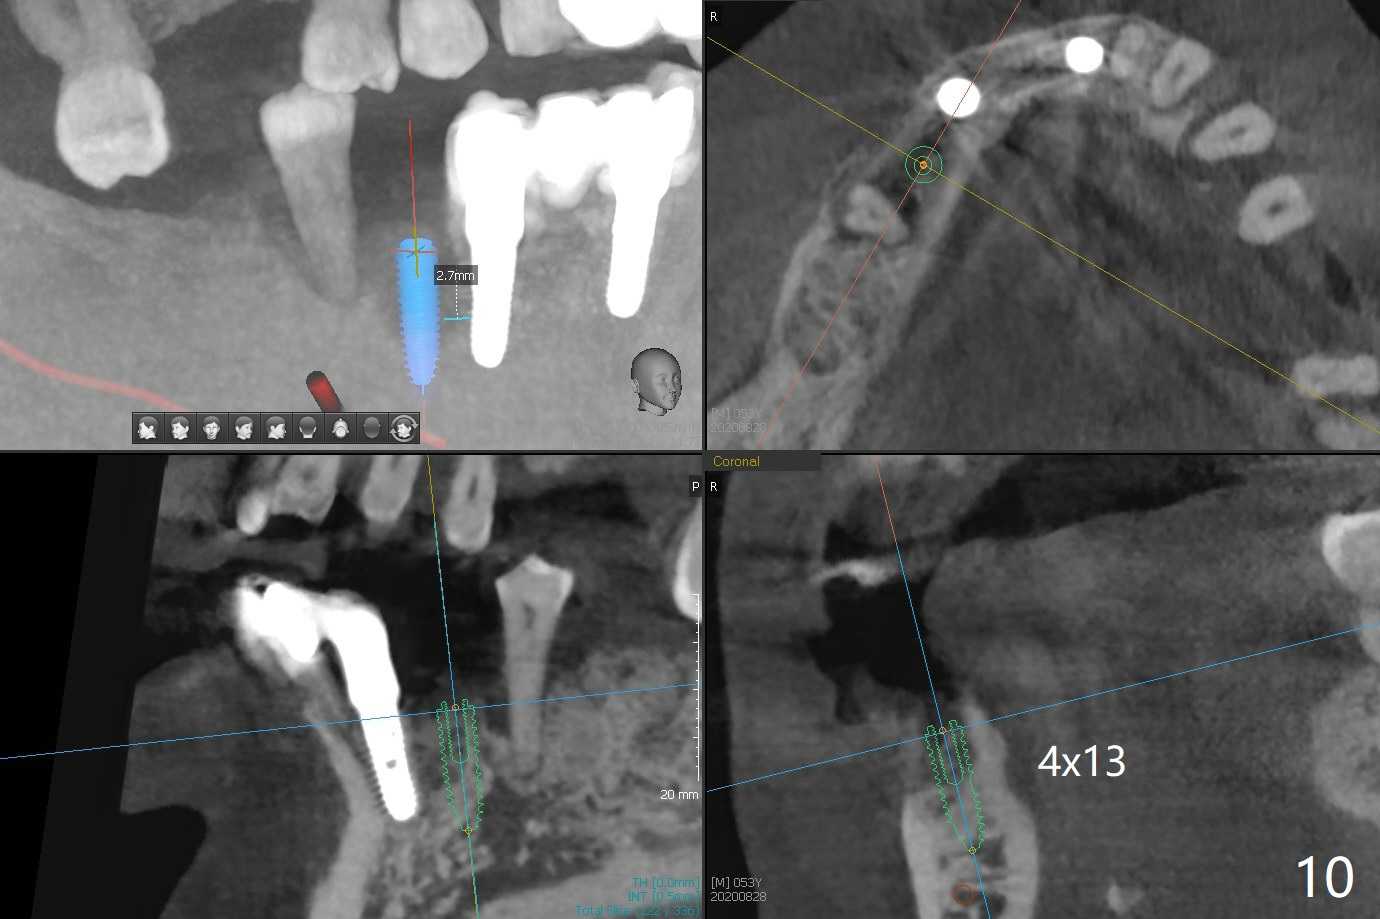

A 52-year-old man with poor dentition has concept of socket preservation when he wants extraction at #30. There is bone loss with the presence of the septum (Fig.1,2 *). Mixture of Vanilla graft and Osteogen is packed around the septum (Fig.3). With blood supply from the septum, the allograft should be more efficiently converted to the native bone than without the septum. The socket is closed with Osteogen plug and suture (Fig.4). In fact the bone height increases by 2.4 mm over the septum 11 months postop (Fig.5,6). In contrast there is apparently no bone regeneration in the socket of #28 four months postop without bone graft (Fig.7). Implant to be placed in the "empty" socket may fail. With bone graft, the ridge at #30 is higher than the surrounding bone 18 months postop (Fig.8 ^) with formation of the cortex on the top of the alveolus <). The average bone density is 1500 units. In contrast, without bone graft, the buccal plate at #28 is missing 11 months postop (Fig.9 >) with average bone density at 500 units. The implant at #28 should be long to engage to the apical native bone (Fig.10) with incision in case of need for bone graft. Sticky bone will be placed mesial to #29.